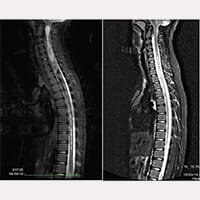

三姐弟的故事分享,神經顱腦脊柱綜合徵、終絲疾病、小腦扁桃體下疝第一型。